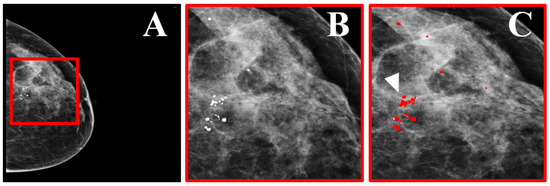

- Loizidou, K.; Skouroumouni, G.; Nikolaou, C.; Pitris, C. Automatic Breast Mass Segmentation and Classification Using Subtraction of Temporally Sequential Digital Mammograms. IEEE J. Transl. Eng. Health Med. 2022, 10, 1–11. [Google Scholar] [CrossRef]

- Breast Masses Dataset with Precisely Annotated Sequential Mammograms|Zenodo, 2022. Available online: https://doi.org/10.5281/zenodo.7179856 (accessed on 13 October 2022).

- Loizidou, K.; Skouroumouni, G.; Savvidou, G.; Constantinidou, A.; Nikolaou, C.; Pitris, C. Identification and Classification of Benign and Malignant Masses based on Subtraction of Temporally Sequential Digital Mammograms. In Proceedings of the 2022 44th Annual International Conference of the IEEE Engineering in Medicine & Biology Society (EMBC), Glasgow, UK, 11–15 July 2022; pp. 1667–1670. [Google Scholar]